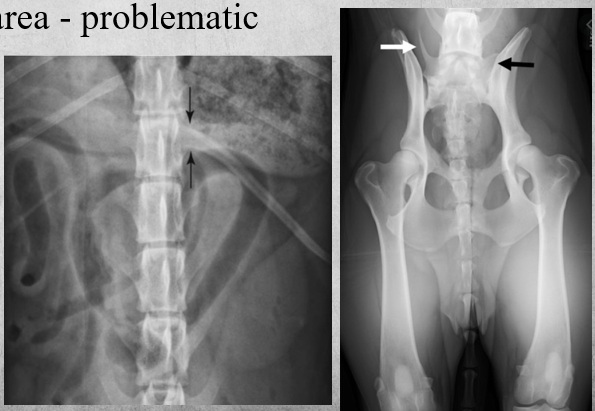

identify anomaly

A

transitional vertebrae

Abnormal vertebra that Shares characteristics with those from an adjacent vertebral segment (can be rudimentary).

When in Lumbosacral area - problematic.

Can be a lumbar vertebra having a rib when it shouldn’t. (right image)

breed predilection, GSD